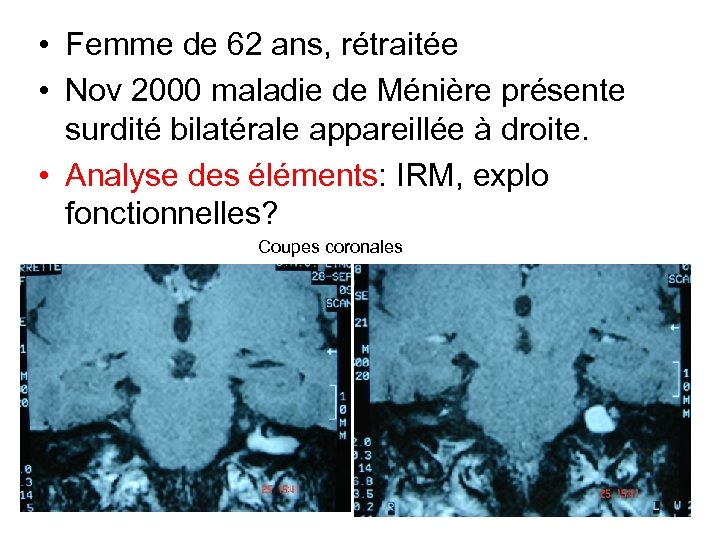

• Femme de 62 ans, rétraitée • Nov 2000 maladie de Ménière présente surdité bilatérale appareillée à droite. • Analyse des éléments: IRM, explo fonctionnelles? Coupes coronales

• Femme de 62 ans, rétraitée • Nov 2000 maladie de Ménière présente surdité bilatérale appareillée à droite. • Analyse des éléments: IRM, explo fonctionnelles? Coupes coronales